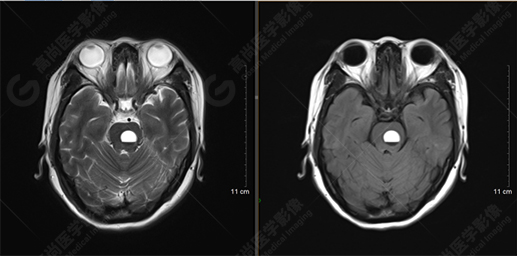

以下是MRI平掃及增強(qiáng)掃描:

T2WI及FLAIR序列

T1WI及T1增強(qiáng)序列

橋腦見(jiàn)一類圓形異常信號(hào)影,直徑約1.3cm,呈T1WI稍高信號(hào),T2WI及FLAIR序列高信號(hào),其內(nèi)見(jiàn)高低信號(hào)分層,增強(qiáng)后無(wú)明顯強(qiáng)化。大腦鐮前部旁見(jiàn)兩個(gè)結(jié)節(jié)影,較大者直徑約1.4cm,呈各序列等信號(hào),增強(qiáng)后呈均勻明顯強(qiáng)化,鄰近大腦鐮增厚、強(qiáng)化。右側(cè)額葉腦白質(zhì)內(nèi)見(jiàn)一斑點(diǎn)狀等T1長(zhǎng)T2信號(hào)影,F(xiàn)LAIR序列呈高信號(hào),增強(qiáng)后無(wú)強(qiáng)化;余腦實(shí)質(zhì)內(nèi)未見(jiàn)局灶性信號(hào)異常,增強(qiáng)后未見(jiàn)異常強(qiáng)化。各腦室、腦池大小、形態(tài)均正常,中線結(jié)構(gòu)居中,幕下小腦無(wú)異常。矢狀面示垂體大小形態(tài)正常,未見(jiàn)局灶性信號(hào)異常。